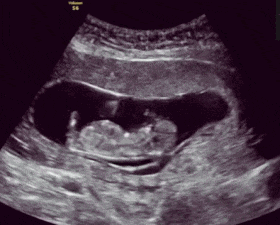

文章插图